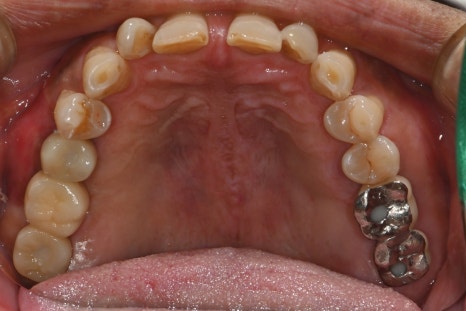

왼쪽 사진: 최종 보철 장착 후 촬영한 파노라마 엑스레이입니다.

오른쪽 사진 : 치료가 마무리된 후의 구강 내 사진입니다.

보철물은 지르코니아 재료로 제작되어 단단하면서도 심미적이며, 자연치와의 조화가 뛰어나게 마무리되었습니다.